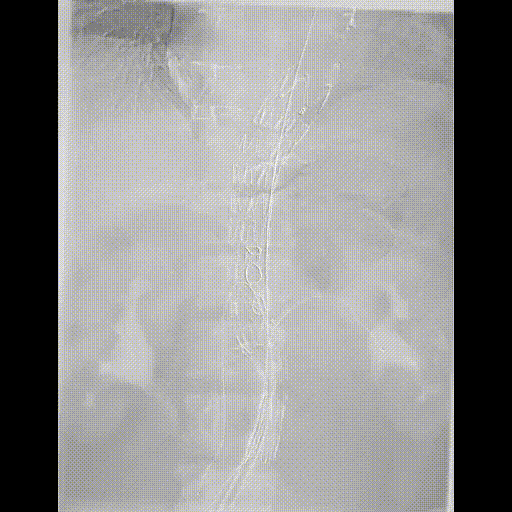

手术方案:内脏区体外三开窗(CA、SMA、LRA),RRA原位开窗。

预三开窗+右肾原位开窗重建

Fustar+Futhrough原位穿刺破膜

预三开窗+肾动脉原位开窗重建